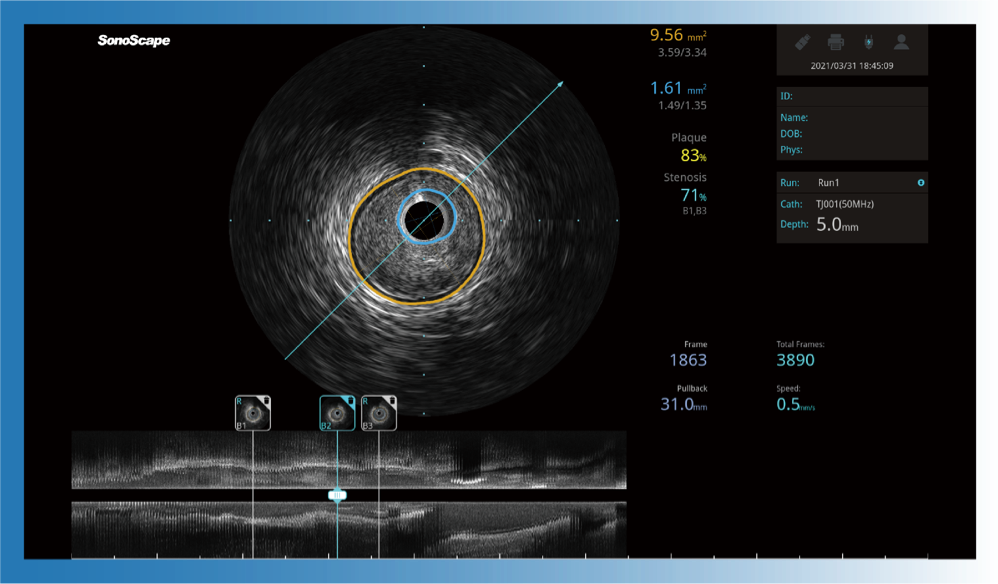

对比传统IVUS导管成像,16877太阳集团宽频IVUS图像的近场支架梁显影更细腻,远场中膜外血管仍清晰可辨,兼顾远中近,兼顾分辨力与穿透深度

一键智能描迹,自动测量斑块负荷、面积狭窄率等指标,准确率高于90%